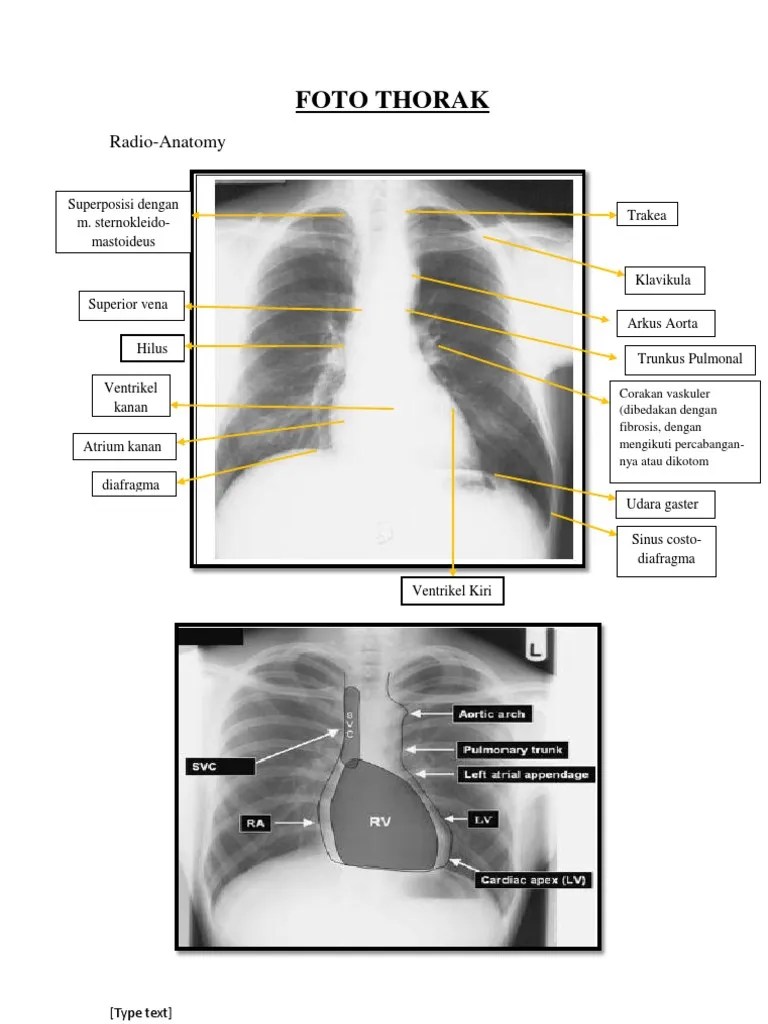

Cara membaca foto thorax (COR): 1.Situs • Dalam keadaan normal cor berada di hemitoraks kiri dan fundus lambung berada di abdo